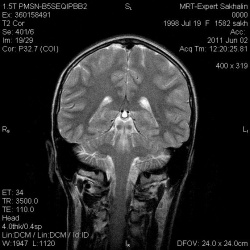

Мужчина 57 лет.Клинически: Мозжечковая атаксия, акинетико-ригидный синдром, пирамидная недостаточность, псевдобульбарный синдром. Развилось в течение года в указанной последовательности.Ваше мнение?P...

26.04.2011 - 18:10